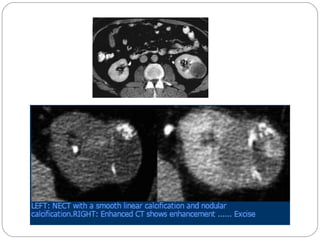

THIN SEPTA HEMORRAGIC CYST

CATEGORY II F

 F = Follow up

 More complex cyst

 Increase in number of septa

and calcifications

 Non enhancing high

attenuation lesions > 3 cm

 May advance to category III

with time and require 6

month follow up